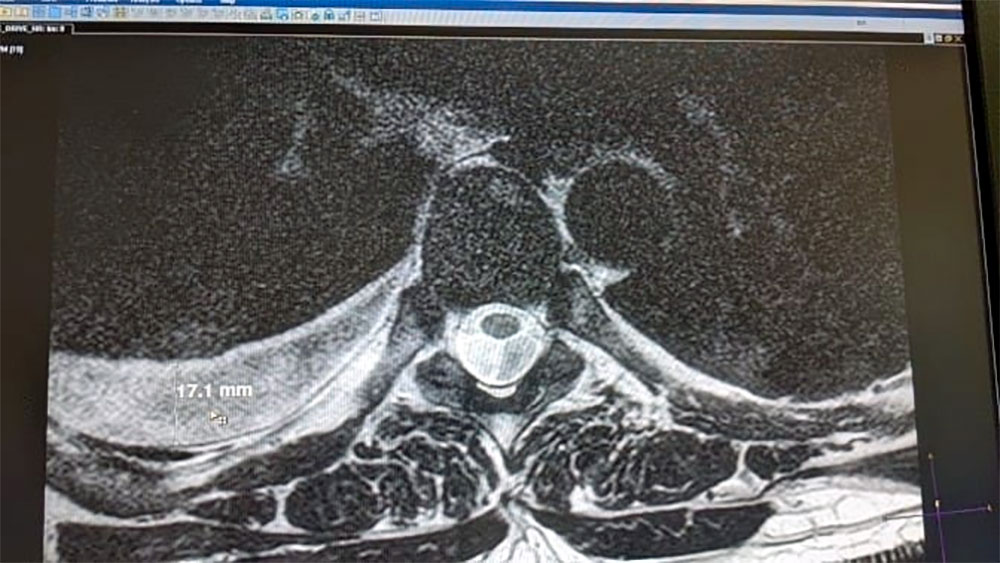

➖МРТ грудного отдела позвоночника — чтобы оценить состояние позвоночника и мягких тканей.

МРТ — выявило воспалительные изменения в плевре.

Причина боли — вовсе не «спина», а плеврит — воспаление оболочки легких.  Повреждения плевральной оболочки и давали «корешковую» симптоматику со стороны позвоночника.